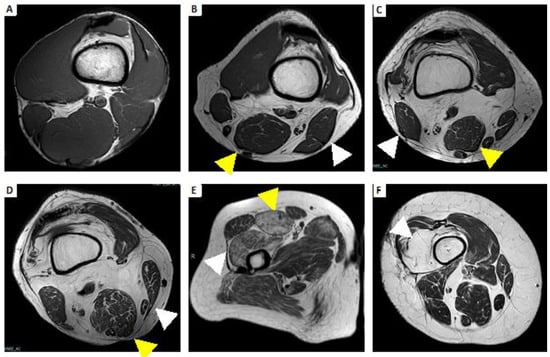

- Dion, E.; Cherin, P.; Payan, C.; Fournet, J.-C.; Papo, T.; Maisonobe, T.; Auberton, E.; Chosidow, O.; Godeau, P.; Piette, J.-C.; et al. Magnetic resonance imaging criteria for distinguishing between inclusion body myositis and polymyositis. J. Rheumatol. 2002, 29, 1897–1906. [Google Scholar]

- Cox, F.M.; Reijnierse, M.; van Rijswijk, C.S.P.; Wintzen, A.R.; Verschuuren, J.J.; Badrising, U.A. Magnetic resonance imaging of skeletal muscles in sporadic inclusion body myositis. Rheumatology 2011, 50, 1153–1161. [Google Scholar] [CrossRef]

- Reimers, C.D.; Schedel, H.; Fleckenstein, J.L.; Witt, T.N.; Pongratz, D.E.; Vogl, T.J.; Nägele, M. Magnetic resonance imaging of skeletal muscles in idiopathic inflammatory myopathies of adults. J. Neurol. 1994, 241, 306–314. [Google Scholar] [CrossRef] [PubMed]

- Ansari, B.; Salort-Campana, E.; Ogier, A.; Le Troter, A.; Marie, B.D.S.; Guye, M.; Delmont, E.; Grapperon, A.; Verschueren, A.; Bendahan, D.; et al. Quantitative muscle MRI study of patients with sporadic inclusion body myositis. Muscle Nerve 2020, 61, 496–503. [Google Scholar] [CrossRef] [PubMed]

| SIDE INVOLVEMENT  | Symmetric | Symmetric | Asymmetric |

| MUSCLE GRADIENT  | Proximal predominance | Proximal predominance | Distal predominance |

| PATTERN OF EDEMA  | Diffuse homogeneous | Peripheral distribution, patchy or honeycomb pattern | Less frequent than fat  degeneration  |

| PATTERN OF MUSCLE FAT INFILTRATION | Less frequent than edema | Less frequent than edema | Predominant fatty  infiltration  |

| FASCIAL INVOLVEMENT  | Not always, less than dermatomyositis | Present | Absent |

| SUBCUTANEOUS INVOLVEMENT | Absent | Significant subcutaneous edema | Absent |

| MUSCLE MORE INVOLVED  | Thigh with global or posterior compartment involvement | Thigh with anterior compartment involvement (quadriceps) | medial head of  gastrocnemius, flexor digitorum profundus, anterior compartment of the thigh  |